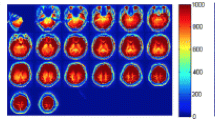

Arterial Spin Labeling (ASL) is an emerging magnetic resonance imaging technique attracting increasing attention in dementia diagnosis only beginning from recent years. ASL is capable to provide direct and quantitative measurement of cerebral blood flow (CBF) of scanned patients, so that brain atrophy of demented patients could be revealed by measured low CBF within certain brain regions through ASL. However, partial volume effects (PVE) mainly caused by signal cross-contamination due to pixel heterogeneity and limited spatial resolution of ASL, often prevents CBF from being precisely measured. Inaccurate CBF is prone to mislead and even deteriorate dementia disease diagnosis results, thereafter. In this paper, a novel dementia disease diagnosis strategy based on ASL is proposed for the first time. The diagnosis strategy is composed of two steps: 1) to conduct pixel-wise PVE correction on original ASL images and 2) to predict dementia disease severities based on corrected ASL images via ranking. Extensive experiments and comprehensive statistical analysis are carried out to demonstrate the superiority of the new strategy with comparison to several existing ones. Promising results are reported from the statistical point of view.